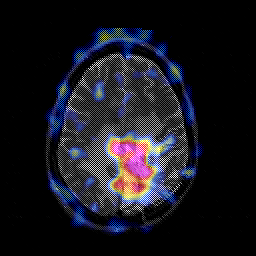

Glioblastoma multiforme overlay -- Slice #37

[Home][Help][Clinical][Tour 1][Tour 2][Tour 3] Slice 37